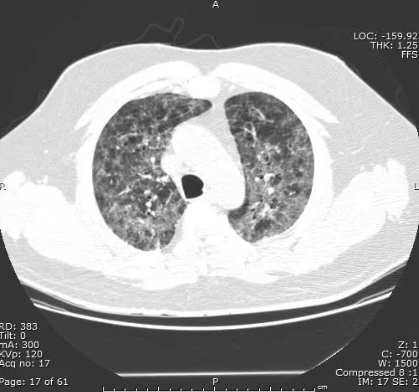

Community acquired pneumonia (CAP)

vs. Pneumocystis jirovecii pneumonia (PCP)

Diffuse bilateral infiltrates

Patchy areas of ground-glass attenuation